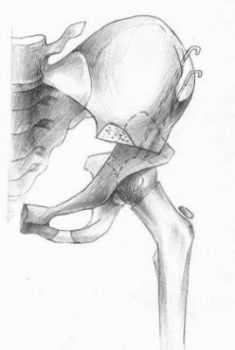

- второй тип, с преобладанием бедренного компонента: деформация шейки бедра (антеторсия либо вальгусная деформация — см. рис 1-2); вертлужная впадина поражена незначительно, либо ее развитие нормальное;

Рис.1Нормальная торсия [3]

Рис.2 Антеторсия [3]